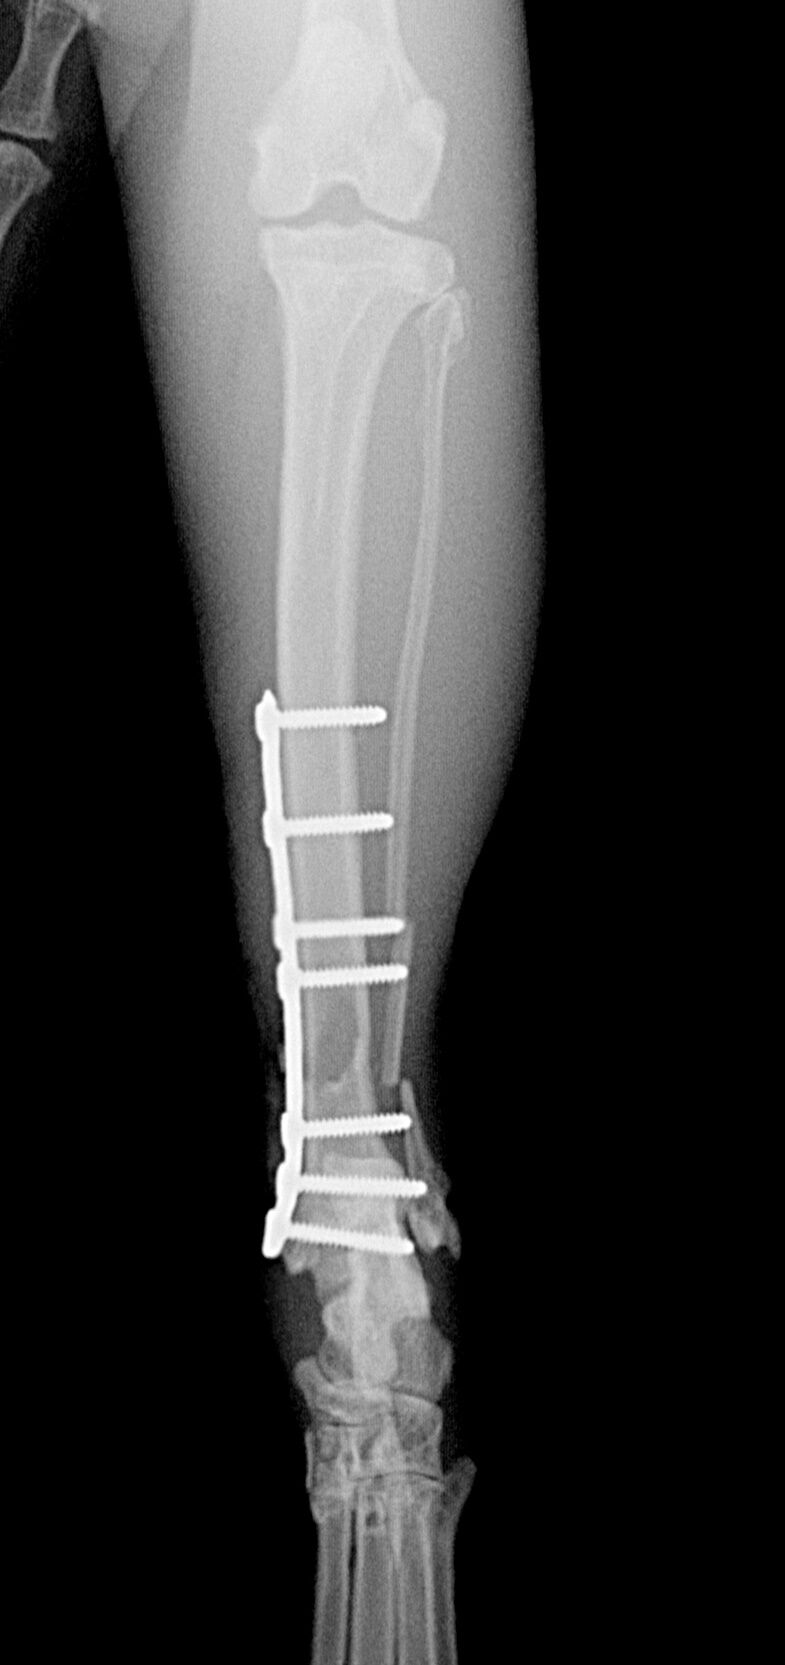

ピンとギブスで固定する方法もあったのですが、脛骨の遠位端(体から離れた端)の骨折だったため、大事を取ってプレートで固定することにしました。それが下の写真です。

術後約1ヶ月は安静気味に過ごしてもらった後は、普通に歩行できていたので終了としました。年齢的なこともあり、プレートは取らずにそのままにしました。